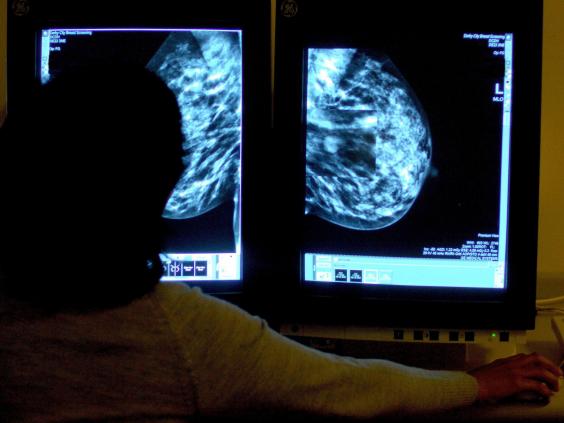

Hundreds of thousands of women were not sent invitations to routine breast cancer screenings (PA)